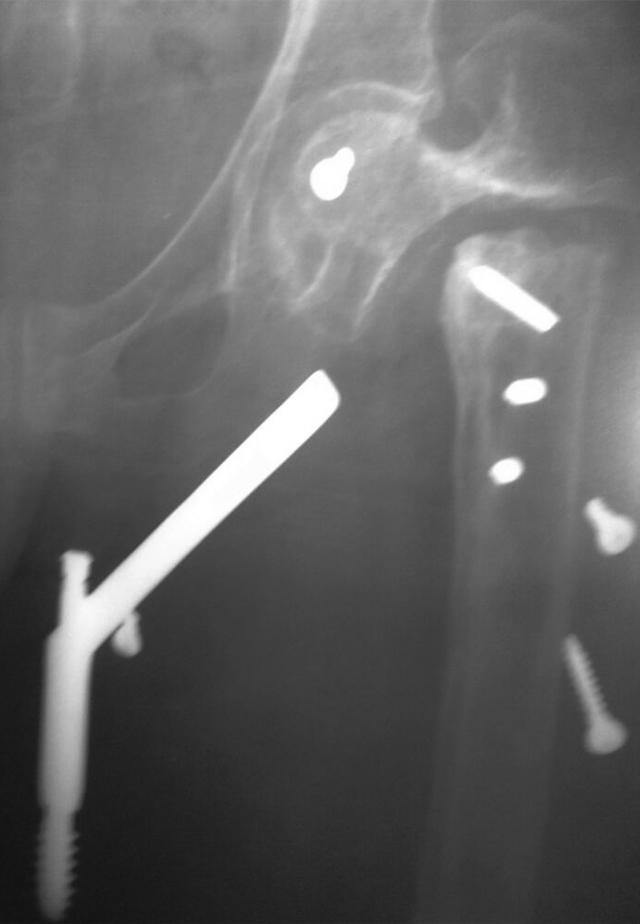

We report a case with implant failure after nailing of an unstable pertrochanteric fracture with dynamic hip screw. The patient presented with a medial sided thigh pain at 5 years after the surgery. Plain radiographs showed nonunion of the fracture with distant migration of assembled hip screw and side plate to the subcutaneous area of the inner thigh.

我们报告了一例采用动力髋螺钉治疗不稳定型转子间骨折后出现植入物失败的病例。该患者在术后5年出现大腿内侧疼痛。X线平片显示骨折不愈合,组装好的髋螺钉和侧板向大腿内侧皮下区域远距离移位。